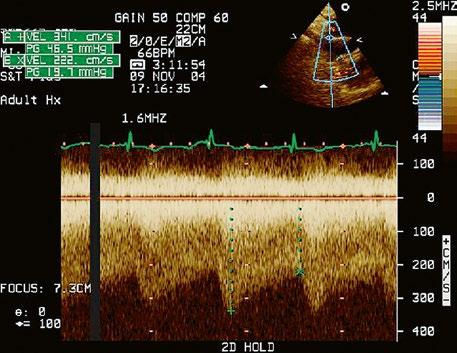

Malé restriktivní defekty komorového septa (Rogerova choroba) nevedou ke vzniku plicní hypertenze ani k srdečnímu selhání. Mají typickou vysokorychlostní dopplerovskou křivku (Obr. 45.35), odpovídající vysokém gradientu mezi levou a pravou komorou v systole a poslechovému nálezu hlučného systolického šelestu.

Obr. 45.35 CW záznam vysokorychlostního dopple rovského toku z levé do pravé komory malým restriktivním defektem komorového septa. Vysoký gradient na komorovém defektu vylučuje vysoký tlak v pravé komoře při plicní hypertenzi nebo při těžké stenóze plicnice.